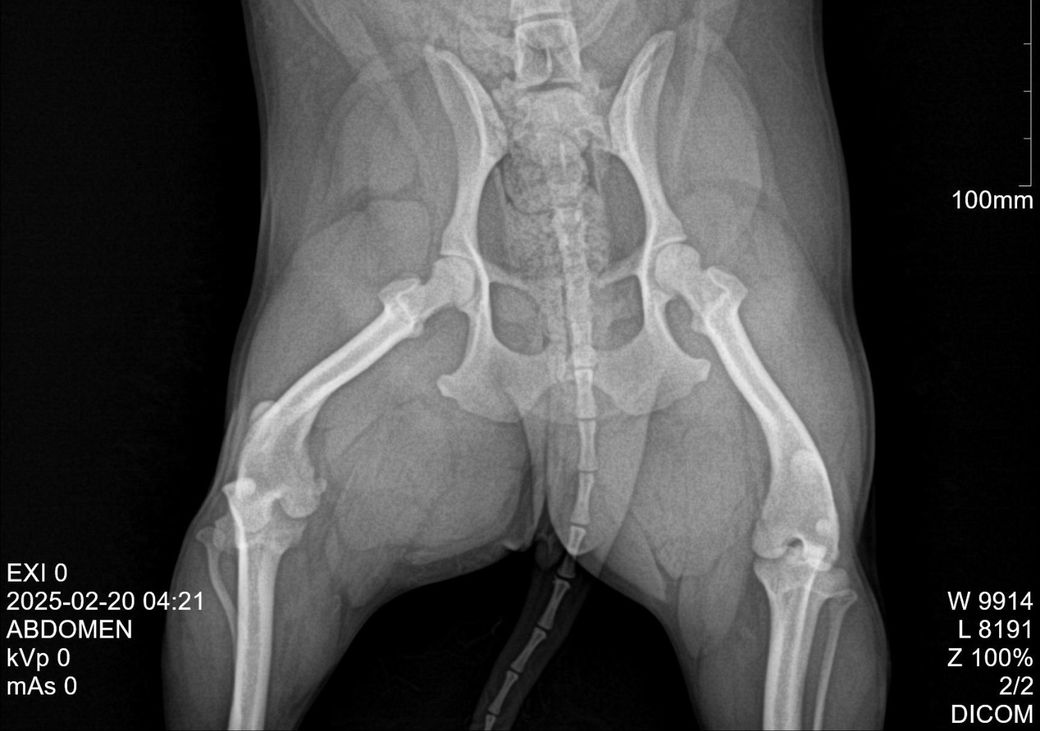

강아지 엑스레이 사진 슬개골 탈구인가요?

말티푸

나이 (개월)

2년 8개월

5

다리를 찍으려던건 아니고 다른 곳 보다가 보인건데 슬개골 탈구 의심됩니다 병원에서 2기라고는 했는데 그건 왼쪽이구요

오늘 거의2주만에 오랜만에.. 놀이방 6시간 맡기는동안 쉴틈없이 뛰어다녔다는데 근육통인지 슬개골이 아파서 인지 우측다리 깽깽이 발을 해서요 지금은 절뚝거리는 정도인데 근육통인가요?ᩚ 참고로 6개월때 작은

사고로 우측다리 골절진단받았었는데 수술은 안하고 성장하면서 붙은 케이스에요 근육을 많이 키워서 괜찮을꺼라 생각했는데 .. 근육통일까요 슬개골이 아파서 그런걸까요?

슬개골 탈구는 숙련된 수의사의 촉진으로 진단하는 질환이지 엑스레이 사진은 퇴행성 관절염을 평가하기 위한 참고진단 검사입니다. 그래서 사진상으로는 슬개골 탈구가 관찰되지 않으나 주치의가 촉진상에서 있다라고 한다면 슬개골 탈구가 있다고 판단하는게 합리적인 추론입니다.